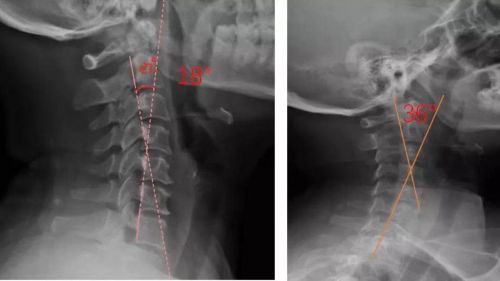

患者適配前后側(cè)位X光,佩戴前18°,適配后36°

我們通過(guò)對(duì)頸部進(jìn)行光學(xué)掃描與頸椎側(cè)位X光檢查,測(cè)量頸椎曲度,由專業(yè)矯形器師結(jié)合患者的情況設(shè)計(jì)個(gè)性化頸椎枕,部分或全部3D打印工藝制作完成,矯正頸椎的生理曲度。患者適配后拍攝X光片,做到精準(zhǔn)矯正與治療,避免使用不適和矯枉過(guò)正。

對(duì)于頸椎病患者,合理設(shè)計(jì)的頸椎枕,能夠緊密適合頸椎,矯正頸椎生理曲度;再根據(jù)頸椎曲度改善情況,隨時(shí)間慢慢調(diào)整3D打印頸椎枕曲度,使變直的頸椎逐漸形成正常的生理曲度,改善頸肩痛的癥狀。